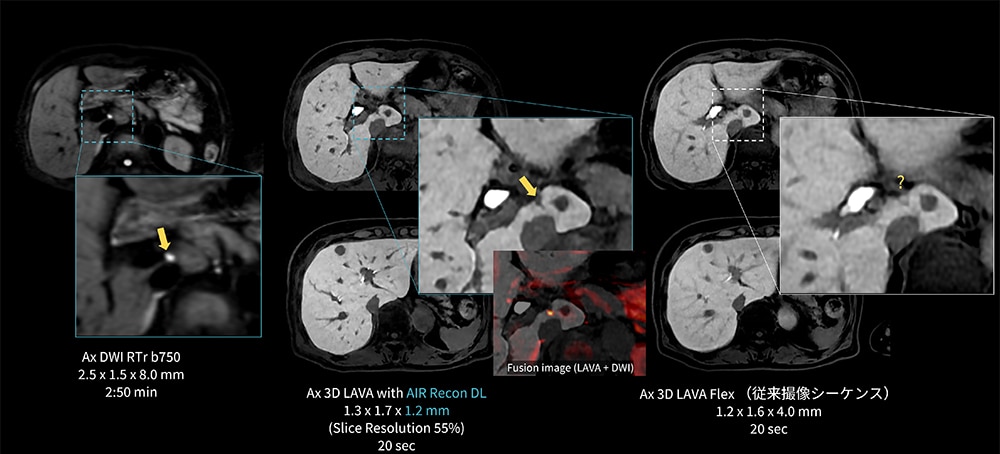

Case6 LAVA/上行結腸癌の多発肝転移

80代、女性。上行結腸癌の多発肝転移でEOB検査を施行。肝臓内に大小多数の結節が認められるが、S1に10㎜大と4㎜大の肝細胞造影相でのEOB取り込み低下あり。

4㎜大の病変(→)については従来撮像条件のLAVA-Flexでは描出が不明瞭であるが、AIR Recon DLを併用したThin sliceのLAVAではDWI高信号に合致した位置に病変が明瞭に描出されている。

図6 Thin slice LAVAを用いた上行結腸癌の多発肝転移における微小病変の描出能向上